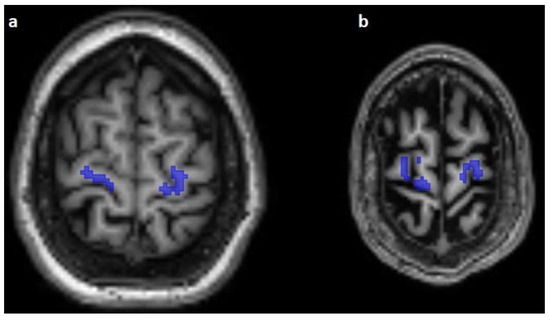

False predicted areas were observed in 23/100 cases (23%) of 3 datasets, with 15 subjects (15/25, 60%) in the Emotion regulation dataset, 7 subjects (7/10, 70%) in the interTVA dataset, and 1 (1/15, 6.66%) subject in the Forrest Gump dataset being affected. According to the course of the pontocerebellar tract, the right hemisphere of the cerebellum was the most common (12/23, 52.17%) falsely segmented area. False prediction in the region parotideomasseterica was observed in 7 cases (7/23, 30.43%), in the pterygoid muscles in 3 cases (3/23, 13.04%), and in the constrictor muscles of the pharynx in 2 cases (2/23, 8.69%) (Figure 4). However, the course of the corticospinal tract was correctly predicted in 19 cases (19/23, 82.60%). In 4 cases, the predicted pathway originated from the centrum semiovale. The number of subjects with falsely segmented areas differed significantly between the groups acquired with Phillips (n = 1) and Siemens scanners (n = 22) (p < 0.001).

Figure 4.

Falsely segmented areas (white) on horizontal T1-weighted images: mm. pterygoidei (a) and cerebellum (b).